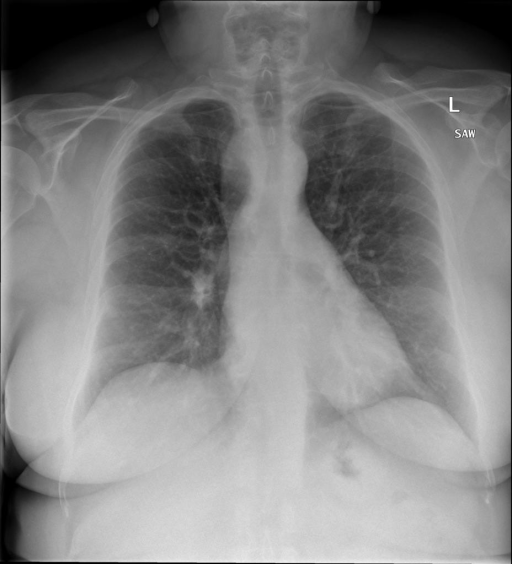

多轮对话:

|X光影像|诊疗报告(医生)|

|:-|:-|

||右侧主动脉突出观察到。心脏大小正常。胸部未发现明显的肺气肿、胸膜积液或可疑的肺部病变。报告指出已知右侧主动脉情况正常。|

```bash